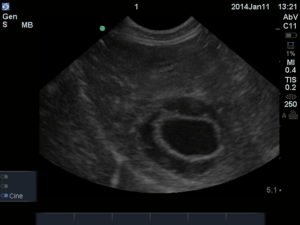

Fig. 1: The classic starting point and depth at the AFAST DH view. Note the thin white (hyperechoic)line that represents the typical unremarkable gallbladder wall; and that adequate depth beyond the diaphragm allows the surveillance for pericardial effusion, the other major rule out to anaphylaxis in collapsed dogs for the gallbladder halo sign.

The sonographic finding of the gallbladder halo sign has been reported to be helpful as a marker for anaphylaxis (AX) in dogs since their shock organ (where most mast cells reside) is their liver and gastro-intestinal tract (unlike humans and cats that have the lungs as their shock organ). The massive histamine release causes acute hepatic congestion due to constriction of hepatic venous outflow (Quantz, JVECC 2009). Of course, other signs are helpful for the diagnosis of AX including acute gastrointestinal signs (vomiting and defecating) with collapse, an elevated lactate, an elevated alanine transaminase (ALT). and hemoconcentration. The image below shows a massive gallbladder halo sign at the AFAST DH view at triage (within minutes of patient arrival). In the following image, you can clearly see pericardial effusion surrounding the heart as imaged at the DH view. Take our AFAST Course to learn more; link for more information- Learn more about AFAST!